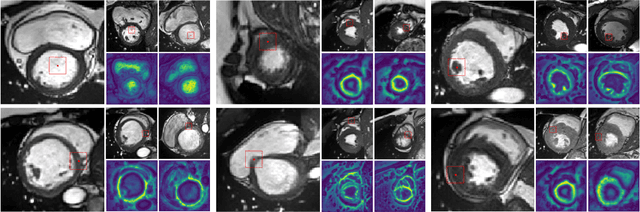

Abstract:Deep learning has revolutionized medical image segmentation, but it relies heavily on high-quality annotations. The time, cost and expertise required to label images at the pixel-level for each new task has slowed down widespread adoption of the paradigm. We propose Pix2Rep, a self-supervised learning (SSL) approach for few-shot segmentation, that reduces the manual annotation burden by learning powerful pixel-level representations directly from unlabeled images. Pix2Rep is a novel pixel-level loss and pre-training paradigm for contrastive SSL on whole images. It is applied to generic encoder-decoder deep learning backbones (e.g., U-Net). Whereas most SSL methods enforce invariance of the learned image-level representations under intensity and spatial image augmentations, Pix2Rep enforces equivariance of the pixel-level representations. We demonstrate the framework on a task of cardiac MRI segmentation. Results show improved performance compared to existing semi- and self-supervised approaches; and a 5-fold reduction in the annotation burden for equivalent performance versus a fully supervised U-Net baseline. This includes a 30% (resp. 31%) DICE improvement for one-shot segmentation under linear-probing (resp. fine-tuning). Finally, we also integrate the novel Pix2Rep concept with the Barlow Twins non-contrastive SSL, which leads to even better segmentation performance.